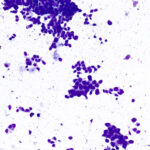

Two Modes of Operation

Deposit and stain mode produces two monolayer slides, one unstained and one Diff-Quik(R) stained in 70 seconds.

Stain only mode Diff-Quik(R) stains touch preps and hand prepared smears for immediate high quality immediate staining in 45 seconds.

Adaptable workflow lets you switch between full slide preparation or stain alone, addressing different biopsy needs automatically.